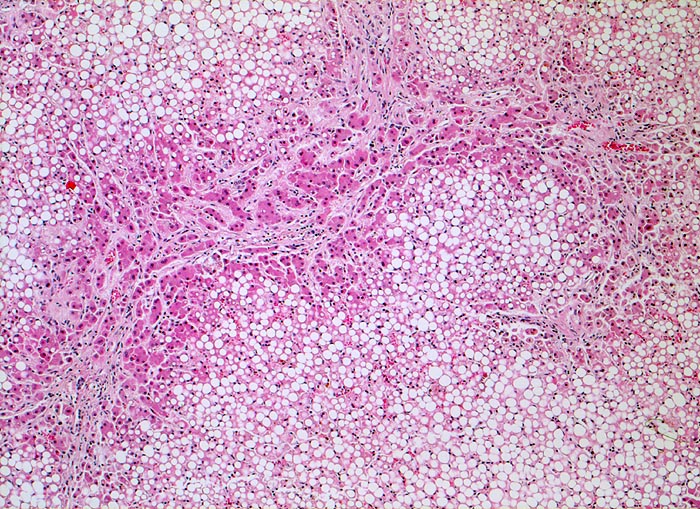

PathoPic – image database / PathoPic ID 4767 - unvollständiger zirrhotischer Umbau, Steatose

unvollständiger zirrhotischer Umbau, Steatose

Leber

Für die Diagnose einer Leberzirrhose wird ein diffuser knotiger Umbau der gesamten Leber gefordert. Die Grenzen zwischen unvollständigem und vollständigem zirrhotischem Umbau sind fliessend.